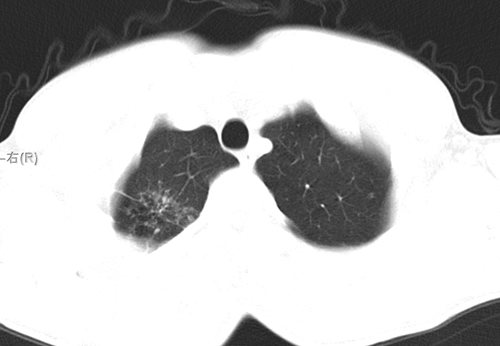

标题: CT24548:男 31 咳嗽 咯血一天 行CT检查 [打印本页]

标题: CT24548:男 31 咳嗽 咯血一天 行CT检查

ct考虑结核 但化验结果示白细胞总数 淋巴均正常,血沉7mm/h不快,请看看结核 支扩还是其他

右肺上叶尖端,后段下叶背段结核伴空洞形成

右肺继发性肺结核伴空洞形成!

好发部位+多种性质病灶=典型tb

右肺继发性肺结核伴右肺下叶背段空洞形成。